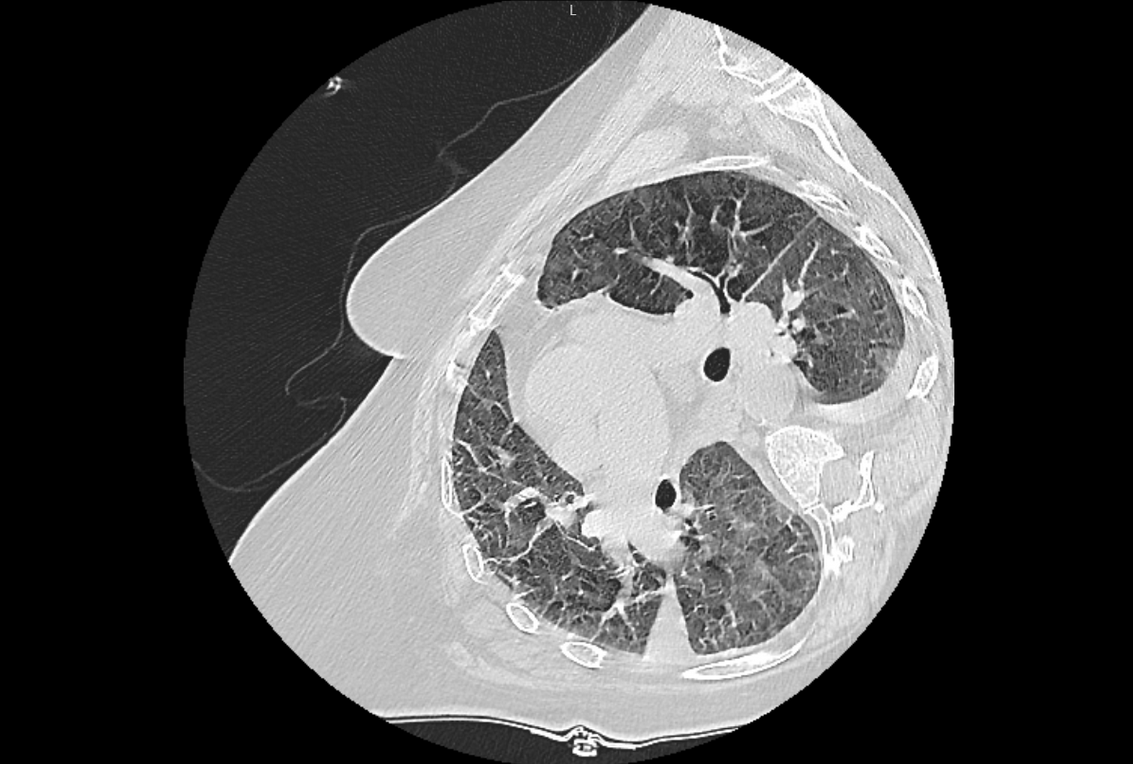

Иногда исследование не является дефективным или редким, но модель при обучении не сталкивалась с такими картинками.

КТ на боку приводило к ошибкам в некоторых патологиях